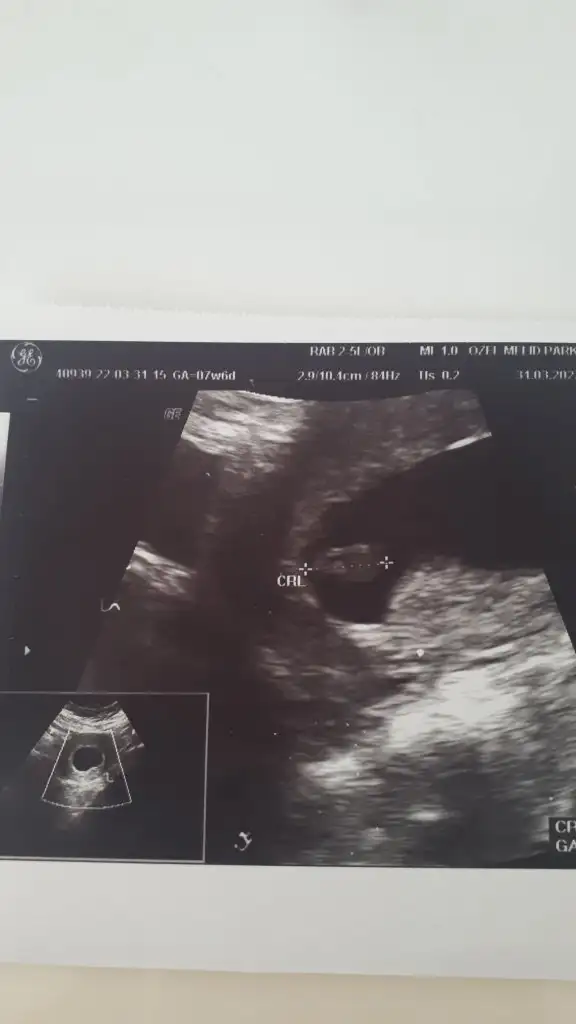

Pasha22 Pasha22 canım bir yakınım ultrason kağıdını atsam bakar mısın cinsiyete 7+4 günlük karından bakılmış 🤩

• IMG_20220404_124327.webp

IMG_20220404_124327.webp

14,7 KB · Görüntüleme: 110